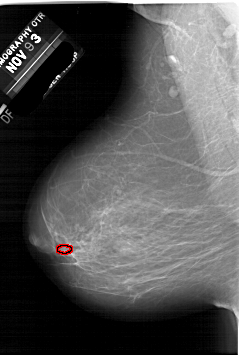

A_1952_1.RIGHT_MLO

RIGHT_MLO LINES 6481 PIXELS_PER_LINE 4096 BITS_PER_PIXEL 12 RESOLUTION 43.5 NON_OVERLAY

FILE: A_1952_1.LEFT_MLO.OVERLAY

TOTAL_ABNORMALITIES 1

ABNORMALITY 1

LESION_TYPE CALCIFICATION TYPE PLEOMORPHIC DISTRIBUTION CLUSTERED

ASSESSMENT 4

SUBTLETY 2

PATHOLOGY BENIGN

TOTAL_OUTLINES 1

BOUNDARY